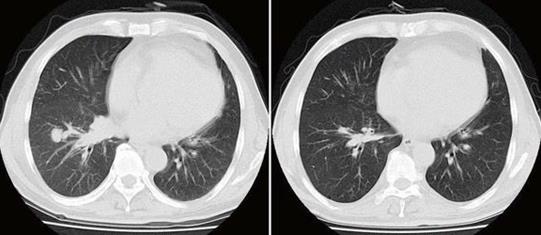

小細(xì)胞肺癌化療后病灶消失

對于小細(xì)胞肺癌的患者來說,由于小細(xì)胞肺癌具有易轉(zhuǎn)移、對化療的短期有效率較好的特點(diǎn),所以不論病情是早期還是晚期,化療均是其主要的治療方法。